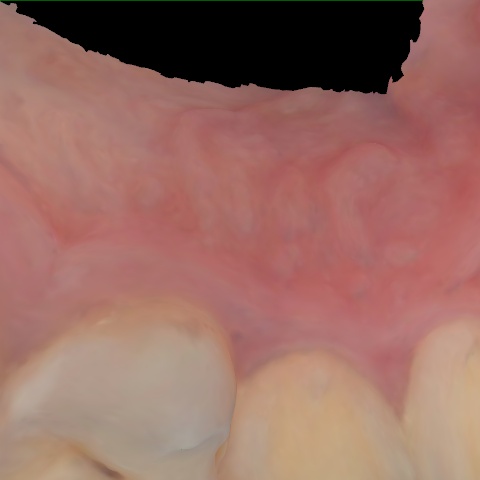

NHD39990

Annotated as "Good"

Original Image Rendering Image